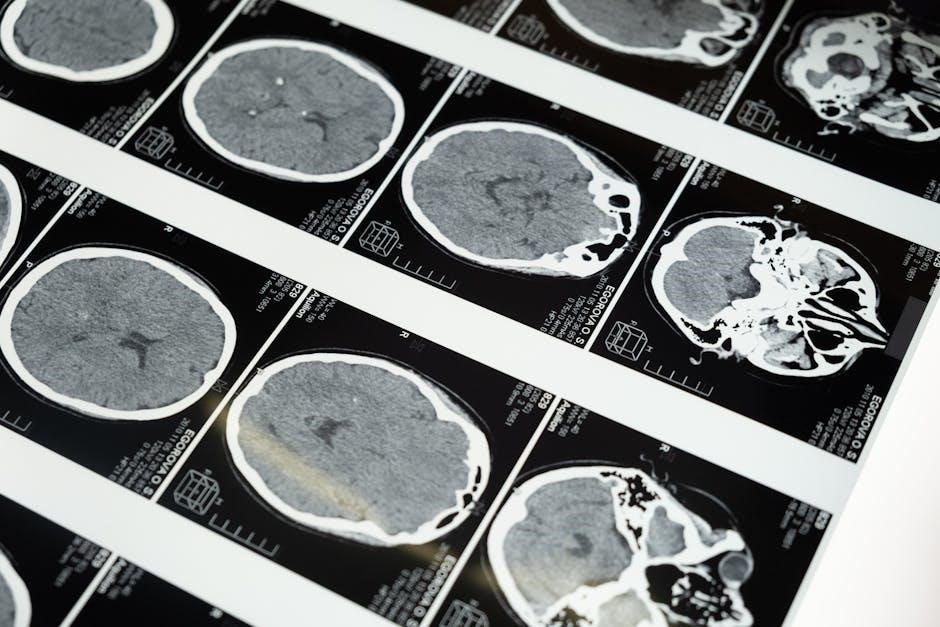

Neurological disorders often present with diverse symptoms, including seizures, muscle weakness, cognitive impairment, and sensory disturbances. Early diagnosis is critical for effective treatment. Physicians use advanced imaging techniques like MRI and CT scans to visualize brain and spine abnormalities. Electroencephalograms (EEG) are employed to assess electrical activity in the brain, aiding in diagnosing conditions such as epilepsy. Lumbar punctures may be performed to analyze cerebrospinal fluid for infections or inflammation. Comprehensive neurological exams evaluate motor skills, reflexes, and coordination. Accurate diagnosis requires a combination of clinical evaluation, patient history, and diagnostic tests. Early detection improves outcomes, emphasizing the importance of timely medical consultation for suspicious symptoms.